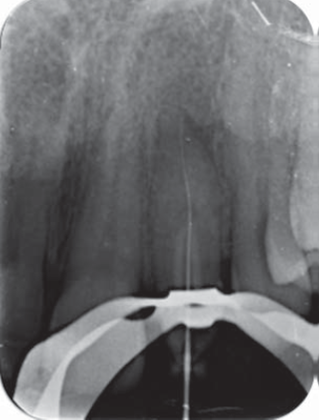

Paciente femenino de 38 años de edad, acude a la Escuela Nacional de Estudios Superiores, Unidad León de la UNAM, al Área de Profundización de Endodoncia y Periodoncia, donde se realizó examen clínico y radiográfico de diente 22. Clínicamente se observa con microdoncia y una corona cónica (Figura 1). Radiográficamente se observa una línea de invaginación radiopaca que penetra la porción radicular, además de una lesión radiolúcida periapical (Figura 2).

Una vez anestesiada la paciente con lidocaína al 2% 1:100000 (ZEYCO, EUA), se aisló con dique de goma y se realizó el acceso con fresa de carburo de #4 (SS-White, EUA). Se localizó el conducto con ayuda del DG16 (Hu-Friedy, EUA) y se instrumentó con técnica crown-down y fuerzas balanceadas con limas K-Flexofile (Dentsply Maillefer, Suiza), la conductometría real se establece en 21 mm con ayuda del localizador Apical Root Zx II J. Morita (MFG Corp, Japón) (Figura 4).